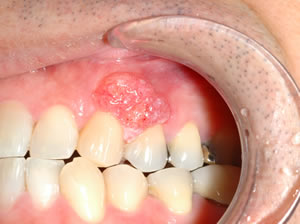

- 歯ぐきのただれやデキモノ

- 白い斑点や赤い斑点(紅板症・白板症)、しこりのようなものが歯ぐきにできることがあります。